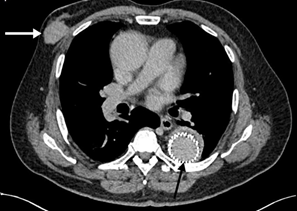

Figure 5 CT scan of the brain showing a solitary intra-axial lesion at grey white matter junction of the left frontal region (black arrow) with thick nodular ring enhancement pattern post contrast. It is associated with extensive white matter edema.